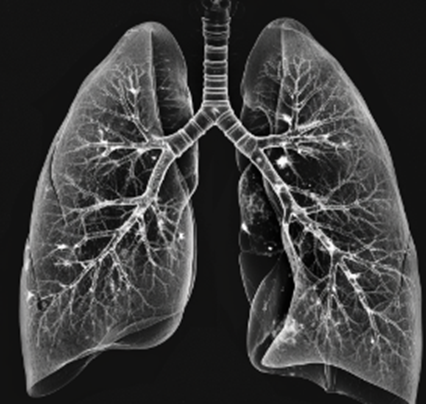

폐결절은 폐 조직 내에 생기는 작은 덩어리로, 일반적으로 크기가 3cm 이하일 때를 말합니다. 크기가 더 크다면 종양으로 간주되며, 조기 발견이 중요합니다. 폐결절은 양성과 악성으로 나눌 수 있습니다. 양성 폐결절은 결핵, 감염, 염증 등으로 인해 발생하며, 대부분 악성으로 발전하지 않습니다. 반면 악성 폐결절은 폐암의 초기 단계일 수 있으며, 조기 발견과 치료가 중요합니다.

폐결절을 발견하는 방법으로는 여러 가지가 있습니다. 가장 기본적인 방법은 흉부 X선 검사입니다. 이 검사는 폐결절을 발견하는 데 유용하지만, 더 정밀한 검사가 필요할 때도 있습니다. 흉부 CT(컴퓨터 단층촬영)는 X선보다 더 정밀하게 결절의 크기와 위치를 확인할 수 있는 검사입니다. 또한 PET-CT(양전자 방출 단층촬영)는 결절의 대사 활동을 확인하여 악성 여부를 판단하는 데 도움을 줍니다.

폐결절의 조기 발견은 매우 중요합니다. 정기적인 검진을 통해 폐결절이 발견되면, 이를 신속히 평가하고 필요한 경우 추가 검사를 통해 양성인지 악성인지를 확인하는 것이 중요합니다. 조기 발견과 적절한 치료는 환자의 예후를 크게 개선할 수 있습니다.